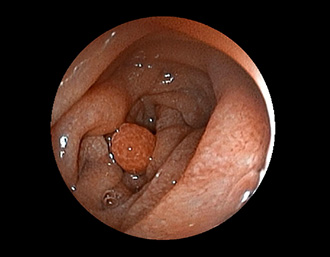

症例7:十二指腸ポリープ(41才男性)

十二指腸乳頭部近傍に炎症性ポリープを認める。経過観察中。

(通常画像)